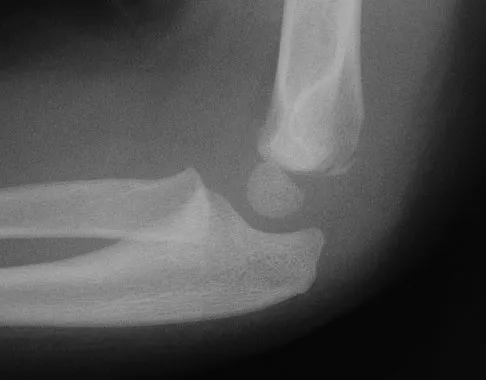

Figure 31 shows the AP and lateral radiographs of the elbow of a 56-year-old man with chronic polyarticular rheumatoid arthritis. His function continues to be limited by pain with activities of daily living. Examination shows that his total arc of motion is 110 degrees. Nonsurgical management has failed to provide relief. Treatment should now consist of

A semiconstrained prosthesis can provide excellent results in carefully selected patients. Because the radiographs show extensive joint destruction with loss of the capitellum and trochlea, a capitellocondylar total elbow (unconstrained) prosthesis is contraindicated. Elbow fusion is poorly accepted, and the radiographs show too much articular destruction for a radial head excision, synovectomy, or interposition arthroplasty to be effective. Ewald FC, Simmons ED Jr, Sullivan JA, et al: Capitellocondylar total elbow replacement in rheumatoid arthritis: Long-term results. J Bone Joint Surg Am 1993;75:498-507.